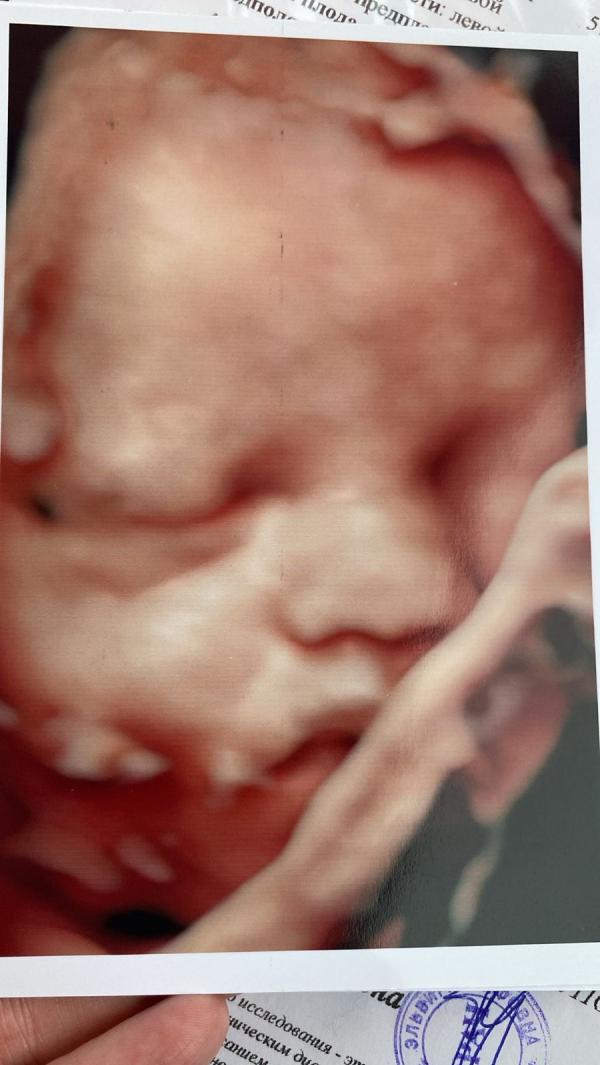

Моя булочка💖быстрее бы уже июль🥰